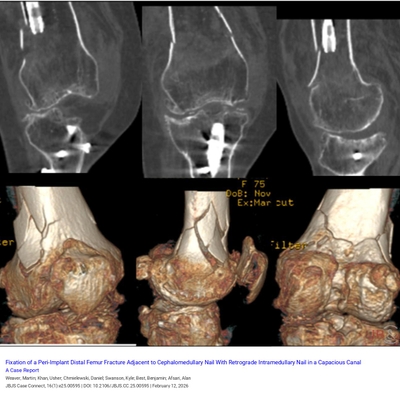

Click on an image below to view more info.